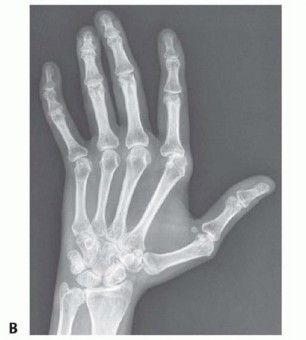

Radiographic evaluation is the ultimate arbiter of surgical candidacy. High-quality, multi-planar radiographs must demonstrate Larsen Grade 1 or 2 changes—specifically, periarticular osteopenia and marginal erosions, but with preservation of the joint space and an absence of significant architectural destruction or fixed volar subluxation. If the joint space is obliterated or if there is severe, uncorrectable volar subluxation with bone-on-bone articulation, soft tissue realignment will inevitably fail. In such advanced cases (Larsen Grades 3-5), the surgeon must pivot to joint arthroplasty (e.g., silicone interpositional arthroplasty) or arthrodesis.

Figure 3: Preoperative radiograph demonstrating classic extensor tendon subluxation and ulnar deviation of the MCP joints, notably with well-maintained joint spaces, making this an ideal candidate for soft tissue reconstruction.

Figure 4: Radiograph depicting extensor tendon subluxation and ulnar deviation with reducible MCP joint subluxation of the index and middle fingers. The lack of severe erosive changes is the key indicator for synovectomy and centralization over arthroplasty.